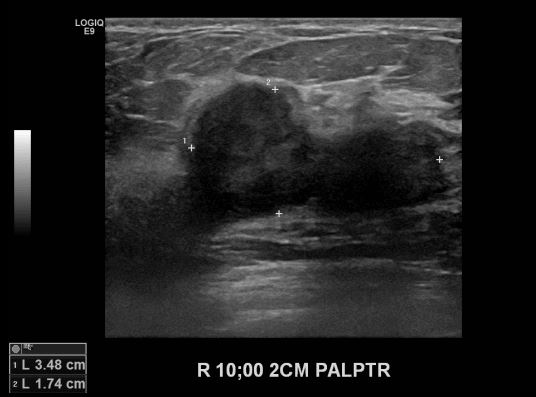

상기환자 우측 유방의 멍울로 내원하신 50대 여성분으로 우측 10시 방향에서 2cm

떨어진 거리의 만져지는 멍울 조직검사 시행하여 우측 침윤성 유관암 진단 되었습니다.